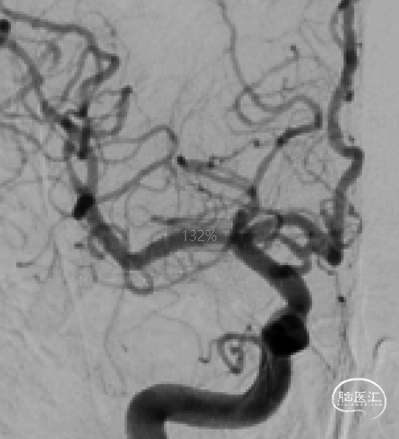

DSA示:右侧大脑中动脉重度狭窄,无颅内出血,参考血管直径为3.2mm,靶病变长度为13.17mm,靶病变直径狭窄程度(WASID法)84.4%。

用2.5-15mm 颅内球囊扩张导管在0.014" 微导丝引导下跨越狭窄段定位后,以6atm工作压扩张30s,后造影示狭窄较前改善。

交换Select Plus微导管上行赛诺神畅 4.5-20mm COMETIU™自膨式颅内药物涂层支架系统跨越狭窄段定位后释放。支架释放后造影显示血流通畅,狭窄明显改善,未使用后扩张球囊,手术成功。

X-perCT颅内未见新鲜出血。

术后6个月随访:

2023-06-28复查脑血管造影示:右侧大脑中动脉狭窄支架术后,支架在位,形态良好,未见再狭窄。

术后18个月随访:

2024-08-20复查脑血管造影示:右侧大脑中动脉支架术后,管腔内通畅。